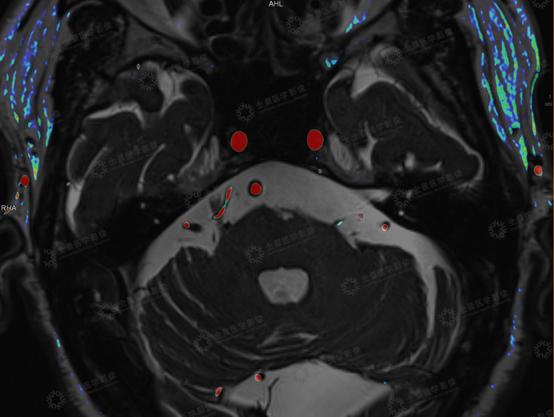

上海全景医学影像诊断中心利用西门子3.0T高场强磁共振扫描仪,采用MRTA序列为:3D TOF MRA序列联合T2 space序列,利用融合校准技术,形成多模态融合MRTA图像,可做到简化阅片,同时可以清晰显示三叉神经与责任血管的解剖关系,明确责任血管来源,并可以利用三维重建进行空间定位,对临床进行术前诊断、术前评估和指导手术方案具有重要的意义。

病史:患者,男,74岁,右侧面部疼痛7年,临床诊断:右侧三叉神经痛